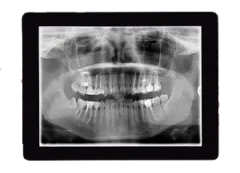

Panorex X-Rays

Panorex X-rays, also known as panoramic X-rays, provide a comprehensive view of the entire mouth in a single image. This includes all teeth, the upper and lower jaws, surrounding structures, and tissues. Panorex X-rays are particularly useful for:

- Assessing the overall alignment and health of the teeth and jaw

- Detecting impacted teeth, cysts and other abnormalities

- Evaluating growth and development in children and adolescents

- Planning complex orthodontic treatments, such as braces or Invisalign